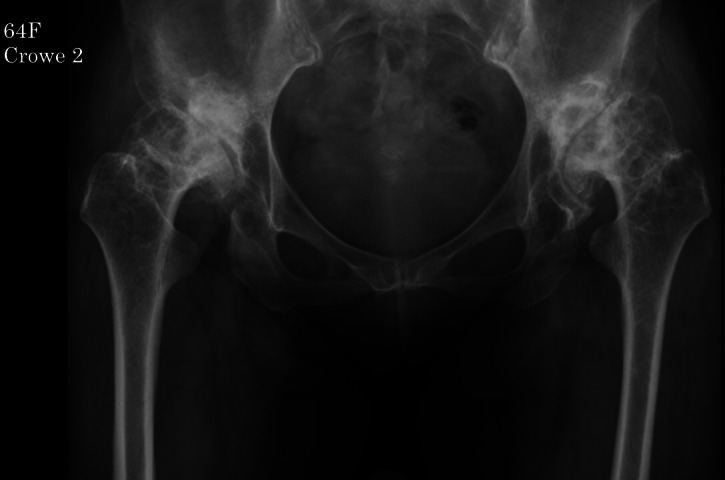

Aims: This study aimed to evaluate the efficacy of porous titanium acetabular augments in primary total hip arthroplasty (THA) for reconstruction of superolateral acetabular bone defects in patients with Crowe II or higher classes of developmental dysplasia of the hip (DDH) or rapidly destructive coxopathy (RDC).

Methods: We conducted a retrospective evaluation of 27 patients (30 hips) who underwent primary THA using cementless cups and porous titanium acetabular augments. The follow-up periods ranged from two to 11 years, with a mean of 5.0 years. The cohort included 22 females (24 hips) and five males (six hips), with a mean age of 67 years (45 to 83) at the time of surgery.